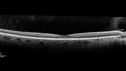

Macular Telangiectasis - Very Mild474 views52 year old female with normal vision and suspicious OCT referred. Multimodal imaging shows very mild mactel (loss of macular pigment, ring on multicolor image and very mild OCT findings)     (0 votes)